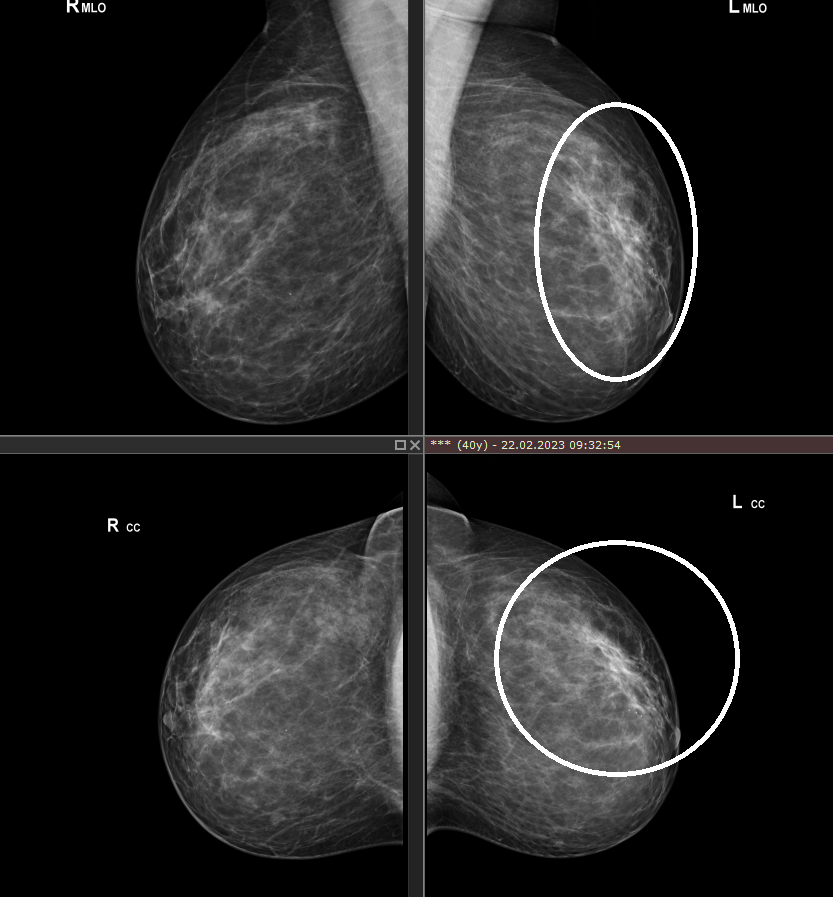

История 40-летней пациентки началась с того, что при плановой маммографии была выявлена тотальная асимметрия (между правой и левой молочной железой), с подозрением на злокачественный процесс в левой молочной железе.

Повышенный риск в отношении рака молочной железы не выявлен.

Асимметрия на маммограммах отмечалась в двух проекциях, была достаточно выраженной, до 7 см в наибольшем измерении, и при раке молочной железы имела бы клиническое отображение (рис.1).

Но ни при осмотре, ни при пальпации изменения структуры железы не были выявлены.